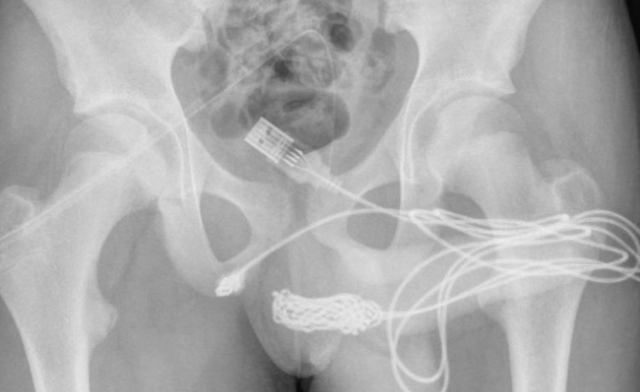

Las radiografías posteriores revelaron que había un verdadero enredo de cable dentro del adolescente. Por ello, los cirujanos hicieron una incisión en la región entre sus genitales y el ano para sacarlo. Primero tiraron del extremo enrollado a través del agujero, cortándolo libre del resto del cable antes de quitar los trozos restantes, literalmente tirando del enchufe.